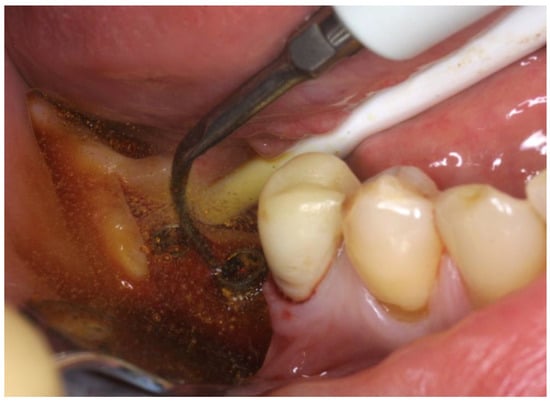

The OHLLT surgical procedure consists of (Figure 2 and Figure 3): local anesthesia; intrasulcular incision for a full thickness periodontal flap; mechanical instrumentation and removal of necrotic tissues with Gracey curettes; ultrasonic instrumentation for supra- and subgingival scaling combined with water–Betadine irrigation (5:1 ratio); air flow device with sodium bicarbonate powder (highly abrasive powder).

Figure 3. Ultrasonic instrumentation with water–Betadine irrigation (5:1 ratio).